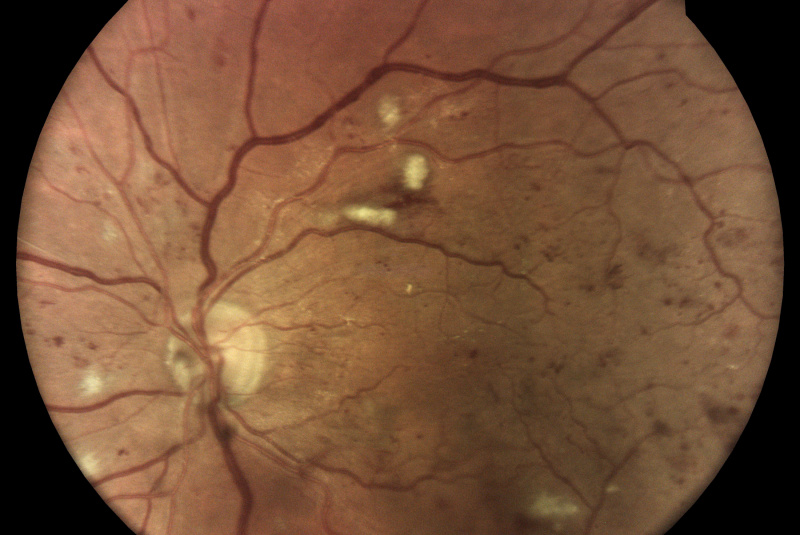

Technológia TrueColor Confocal od iCare prekračuje limity konvenčných zariadení na zobrazovanie fundusu a SLO tým, že kombinuje tie najlepšie výhody z oboch. Jednoducho povedané, fundus fotoaparáty poskytujú vysokú vernosť farieb a systémy SLO produkujú vysokú ostrosť, čistotu, celkovú presnosť a detaily v obrazoch. Keď sa tieto funkcie skombinujú, vytvárajú obraz krajiny sietnice špičkovej kvality vo verných farbách.

Aby bolo možné diagnostikovať a sledovať bežné patológie, ako je diabetická retinopatia, zariadenia na zobrazenie očného pozadia musia byť schopné kombinovať veľké rozlíšenie, vysoký kontrast a vysokú vernosť farieb. To umožňuje zachytiť malé znaky a detaily a rozlišovať medzi jednotlivými zmenami, ktoré by ste mohli inak ľahko prehliadnuť. Zatiaľ čo štandardné systémy SLO majú vysokú jasnosť, ostrosť a kontrast, tradičné fundus kamery ponúkajú vysokú vernosť farieb, konvenčné zobrazovacie riešenia tieto dve veci nekombinujú!

Monochromatické lasery používané v štandardných systémoch SLO môžu vďaka konfokálnemu optickému enginu poskytnúť vysokú ostrosť a vysoký kontrast obrázkov. Na druhej strane nedokážu zachytiť sietnicu v jej skutočných farbách.

Zobrazovacie systémy fundus generujú obrazy s prirodzenými farbami iba vtedy, ak využívajú biele svetlo: to znamená, že všetky vlnové dĺžky viditeľného spektra sú prítomné v osvetľovacom lúči použitom na získanie obrazu sietnice. Na získanom zábere je možné rozlíšiť rôzne farebné detaily.

Naopak systémy využívajúce monochromatické svetelné zdroje, ako sú systémy SLO, používajú na osvetlenie sietnice iba špecifické vlnové dĺžky. Preto poskytujú pseudofarebné zábery, ktorým chýbajú niektoré spektrálne zložky a výsledkom sú chýbajúce informácie alebo farebné artefakty.

iCare sa vyznačuje používaním bieleho svetla LED v kombinácii s konfokálnou optikou, ktorá pomáha získavať vysokokvalitné snímky sietnice so zvýšenou vernosťou farieb.